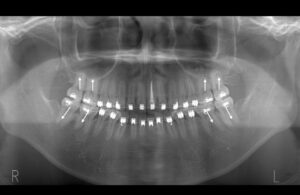

親知らずによって持ち上げられていた臼歯部を圧下していく。臼歯部を圧下しつつ、

前歯を咬合させるように顎間ゴムで力を少しずつかけていく。

少しずつ少しずつ

矯正治療終了